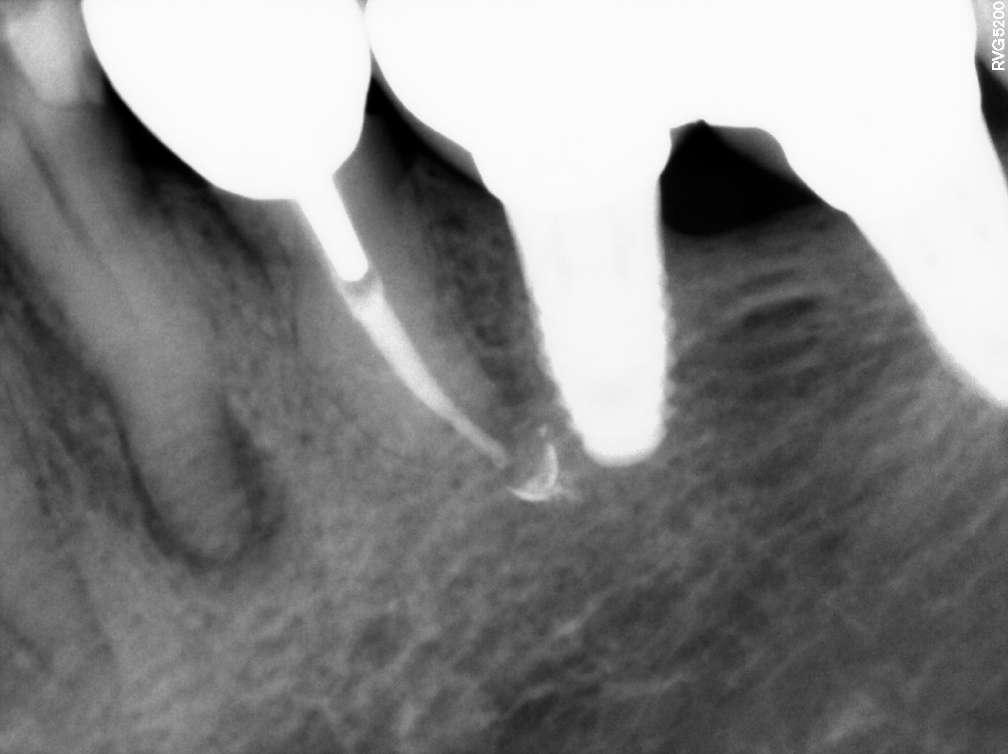

Divergierende Kanäle (zwei Kanäle, die zusammen beginnen und sich dann im mittleren / apikalen Teil der Wurzel trennen) stellen ein klinisches Problem in der Endodontie dar, insbesondere bei der Verwendung traditioneller NiTiInstrumente. Aufgrund des superelastischen Verhaltens der Legierung können die Instrumente dem gleichen Kanal folgen (und zwar dem, der gerader ist) aber es ist schwieriger, den zweiten zu finden, insbesondere dann, wenn man den Eingang unmöglich wegen seiner Tiefe in der Wurzel sehen kann.

Der vorliegende Fall zeigt den klinischen Vorteil der Verwendung einer Einzelfeil-Reziprokationstechnik mit einer wärmebehandelten vorgebogenen martensitischen Feile (Edge One Fire) bei der Behandlung divergierender Kanäle auf.

Untere Prämolaren können manchmal zwei oder drei Kanäle aufweisen. Eine solche ungewöhnliche Anatomie ist oft mit engen, stark gekrümmten, konfluenten oder divergierenden Kanälen verbunden. Der letzte Fall ist sehr komplex und erfordert in der Regel den Einsatz von Instrumenten, welche in zwei verschiedenen Kanälen ( daher flexibel und präbendal ) mit unterschiedlichen Winkelstellungen ausgerichtet werden können. Ein angemessener Gleitpfad hilft auch bei der NiTi-Formung, er löst aber nicht immer das Problem. Daher wurde im vorliegenden Fall die primäre EinzelfeileReziproziertechnik EOF verwendet. Die Instrumente wurden in ihrem apikalen Teil vorgeformt, in die beiden verschiedenen Kanäle eingeführt und dann aktiviert. Die Wahl der Instrumente war effektiv, weil die mechanischen Eigenschaften des EOF-Primärs (flexibel und vorgebogen) es ermöglichen, präzise und einfach in jeden Kanal eingeführt zu werden und diese dann zu behandeln. Die Verwendung einer einzigen Feiltechnik ermöglichte es, sich der Herausforderung eines divergierenden Kanals nur einmal zu stellen, was Zeit spart und die Komplexität reduziert. Die Verwendung traditioneller Instrumente kann in vielen Fällen helfen, den Weg mit kleineren und flexibleren Instrumenten zu finden, aber nicht mit größeren. Durch die Verwendung von nur einer Feile erwies sich das gesamte Verfahren als einfacher und schneller, sodass beide Kanäle korrekt geformt, gereinigt und abgedichtet werden konnten.

Eine Single-File-Reziprozierungstechnik mit einer wärmebehandelten vorgebogenen martensitischen Feile (Edge One Fire) erwies sich als ausgezeichnete, einfache und schnelle Option für die Instrumentierung von divergierenden Kanälen.

Komplexe Kanalanatomien erfordern den rationalen Einsatz von NITIInstrumenten, indem die beste Option für den Fall in Bezug auf Effizienz, Sicherheit und Einfachheit ausgewählt wird. Die mechanischen Eigenschaften von EOF ermöglichen es, divergierende Kanäle mit großer Wirksamkeit zu behandeln, wobei iatrogene Fehler oder Komplikationen vermieden werden können.